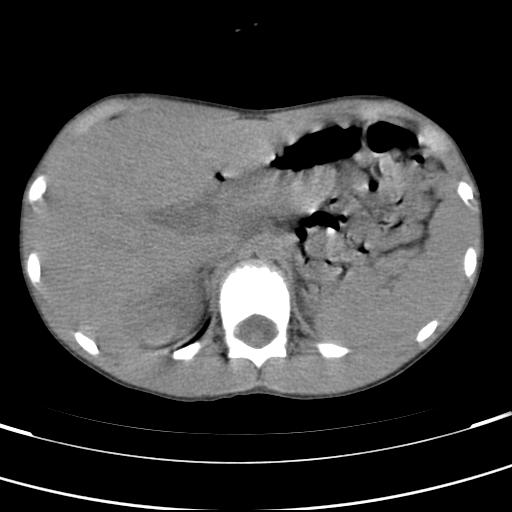

标题: PED3157:左肾缺如,请教脾脏的改变?、、

男孩,9岁。胃部不适。

脾脏位于左侧,但数个脾脏呈分离状态,左肾缺如,右肾代偿肥大。考虑多脾综合征。